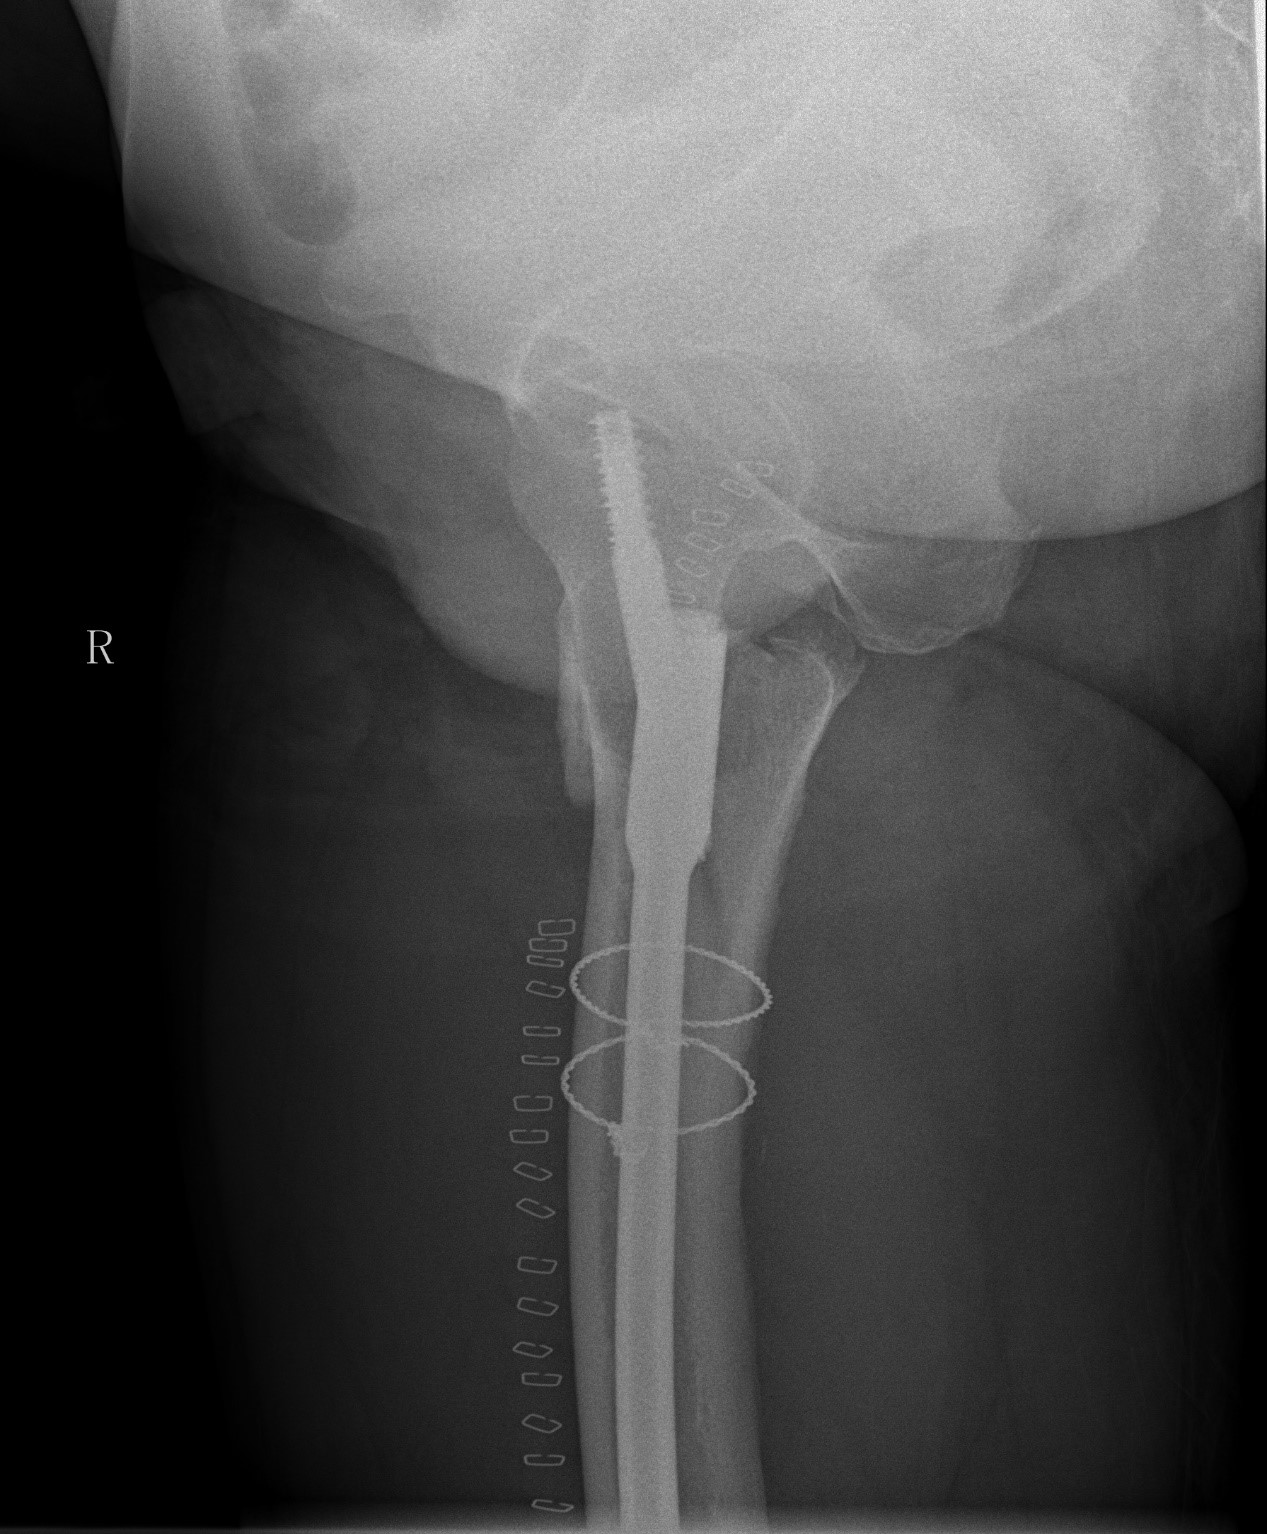

案例二:51岁男性意外摔伤

患者情况:吴先生因路面湿滑不慎摔倒,导致右髋部疼痛并活动受限,经检查确诊为股骨粗隆间骨折。

治疗难点:

1.骨折部位解剖重建的准确性;

2.内固定材料的选择及固定强度的保障。